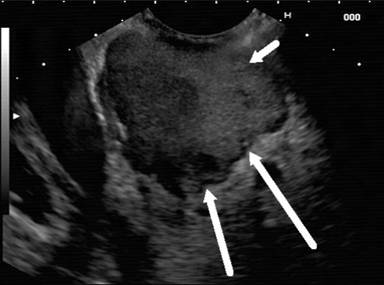

Endoscopic ultrasound (EU) (Figure 2) revealed diffusely enlarged of pancreas. There was a mixed echoic mass lesion 37-50 mm at the head of pancreas (R/O walled off necrosis) with adhesion to portal vein and SMV (superior mesenteric vein). On the other hand the CBD (common bile duct) was 9 mm.

Figure 2. Diffusely enlarged of pancreas and echoic mass lesion 37-50 mm at the head of pancreas (R/O walled off necrosis) with adhesion to portal vein and SMV. |